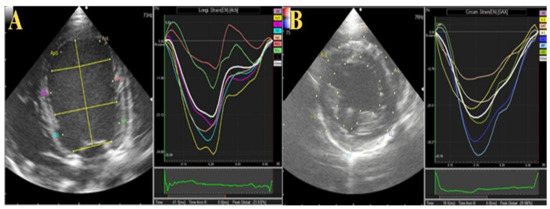

Figure 1. Two-dimensional echocardiographic localization of the implanted TEER (yellow arrowhead). Successful localization of TEER during operation through transesophageal-guided echocardiography (A). For post-operative follow-up, transthoracic echocardiography from left apical (B), right long axis (C), and right short-axis views (D) were used. LA left atrium; LV, left ventricle.

Implantation of the TEER was performed in two female beagles, aged 2 and 2.5 years and weighing 8.6 and 10.3 kg, respectively. These two dogs were healthy, based on physical examinations, hematobiochemical profile, conventional echocardiography, and urinalysis. The detailed procedure of the surgical approach has been previously described [15]. Briefly, the dogs were maintained on general anesthesia using 2–3% isoflurane (Pfizer, Tokyo, Japan) after induction with propofol (Fresenius Kabi, Tokyo, Japan). The TEER was guided by a transesophageal echocardiography (TEE) probe in the median longitudinal and transverse views [15]. Heparinized normal saline (100 IU/kg) was administered intravenously after exposing the heart at the left sixth intercostal space via thoracotomy. The pericardium was incised and the apical area leaked. After placing a purse-string on the cardiac apex, the TEER MV repair delivery system was inserted through the cardiac apex first into the left ventricle and then into the left atrium under echocardiographic guidance. The MV was captured, and the TEER was deployed after the clamp position was confirmed (Figure 1). The delivery system was released, and the cardiac apex were sutured by the purse-string. Pericardium, thoracic wall and skin were sutured by 3-0 Prolene, PDS and Nylon, respectively. No medication was given to the dogs during the operation. Postoperative recoveries were monitored by a critical care team consisting of licensed veterinarians. During the postoperative period, clinical signs, echocardiography, electrocardiogram, blood pressure, blood picture, serum chemistry, and urine volume were monitored [9]. Additional proper administration will be executed by the critical care team, but in these two dogs, we did not prescribe any drugs. Postoperative antibiotics (ampicillin, Meiji Seika, Tokyo, Japan) and painkillers (buprenorphine hydrochloride, Otsuka Pharmaceutical, Tokyo, Japan) were administered for 3 days. Clopidogrel (Nichi-Iko, Tokyo, Japan) was administered at 2 mg/kg for 1 week postoperatively.

The detailed echocardiographic parameters are listed in Table 1. The left ventricular dimensions showed no dramatic changes after the surgeries. The fractional shortening was increased postoperatively in both dogs compared with the baseline, but this increase was much higher in dog 2. The mitral inflow velocity waves (E and A) were significantly increased after the operation and throughout the investigation period (Figure 2). The mitral valve orifice in both dogs was slightly narrowed after the operations (2–3 mm difference) at the second and third weeks. In addition, the stenosis was not progressive and both dogs showed slight enhancement of the mitral orifice at the fourth week. Concomitantly, the LA/Ao, early diastolic inflow to myocardial velocity (E/e’), and mitral valve regurgitation velocity (MR) were increased in both dogs after surgery.